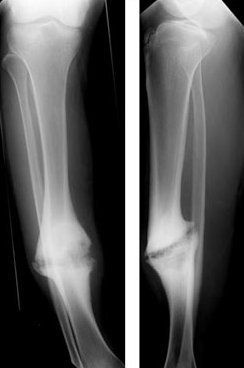

Non-union refers to inability of the bone to heal or no healing potential demonstrated by bone. There are three types of non-union: 1. HYPERTROPHIC NON-UNION: Hypertrophic non-union occurs due to excessive movements on the fracture site 2. ATROPHIC NON-UNION: Atrophic non-union occurs due to biological factors e.g., blood supply and lack of stimulus to stimulate bone growth 3. INFECTIVE NON-UNION: Infections delays the healing of the bone Reference: Bailey and Love's Short Practice of Surgery Image via: https://en.wikipedia.org/wiki/Nonunion